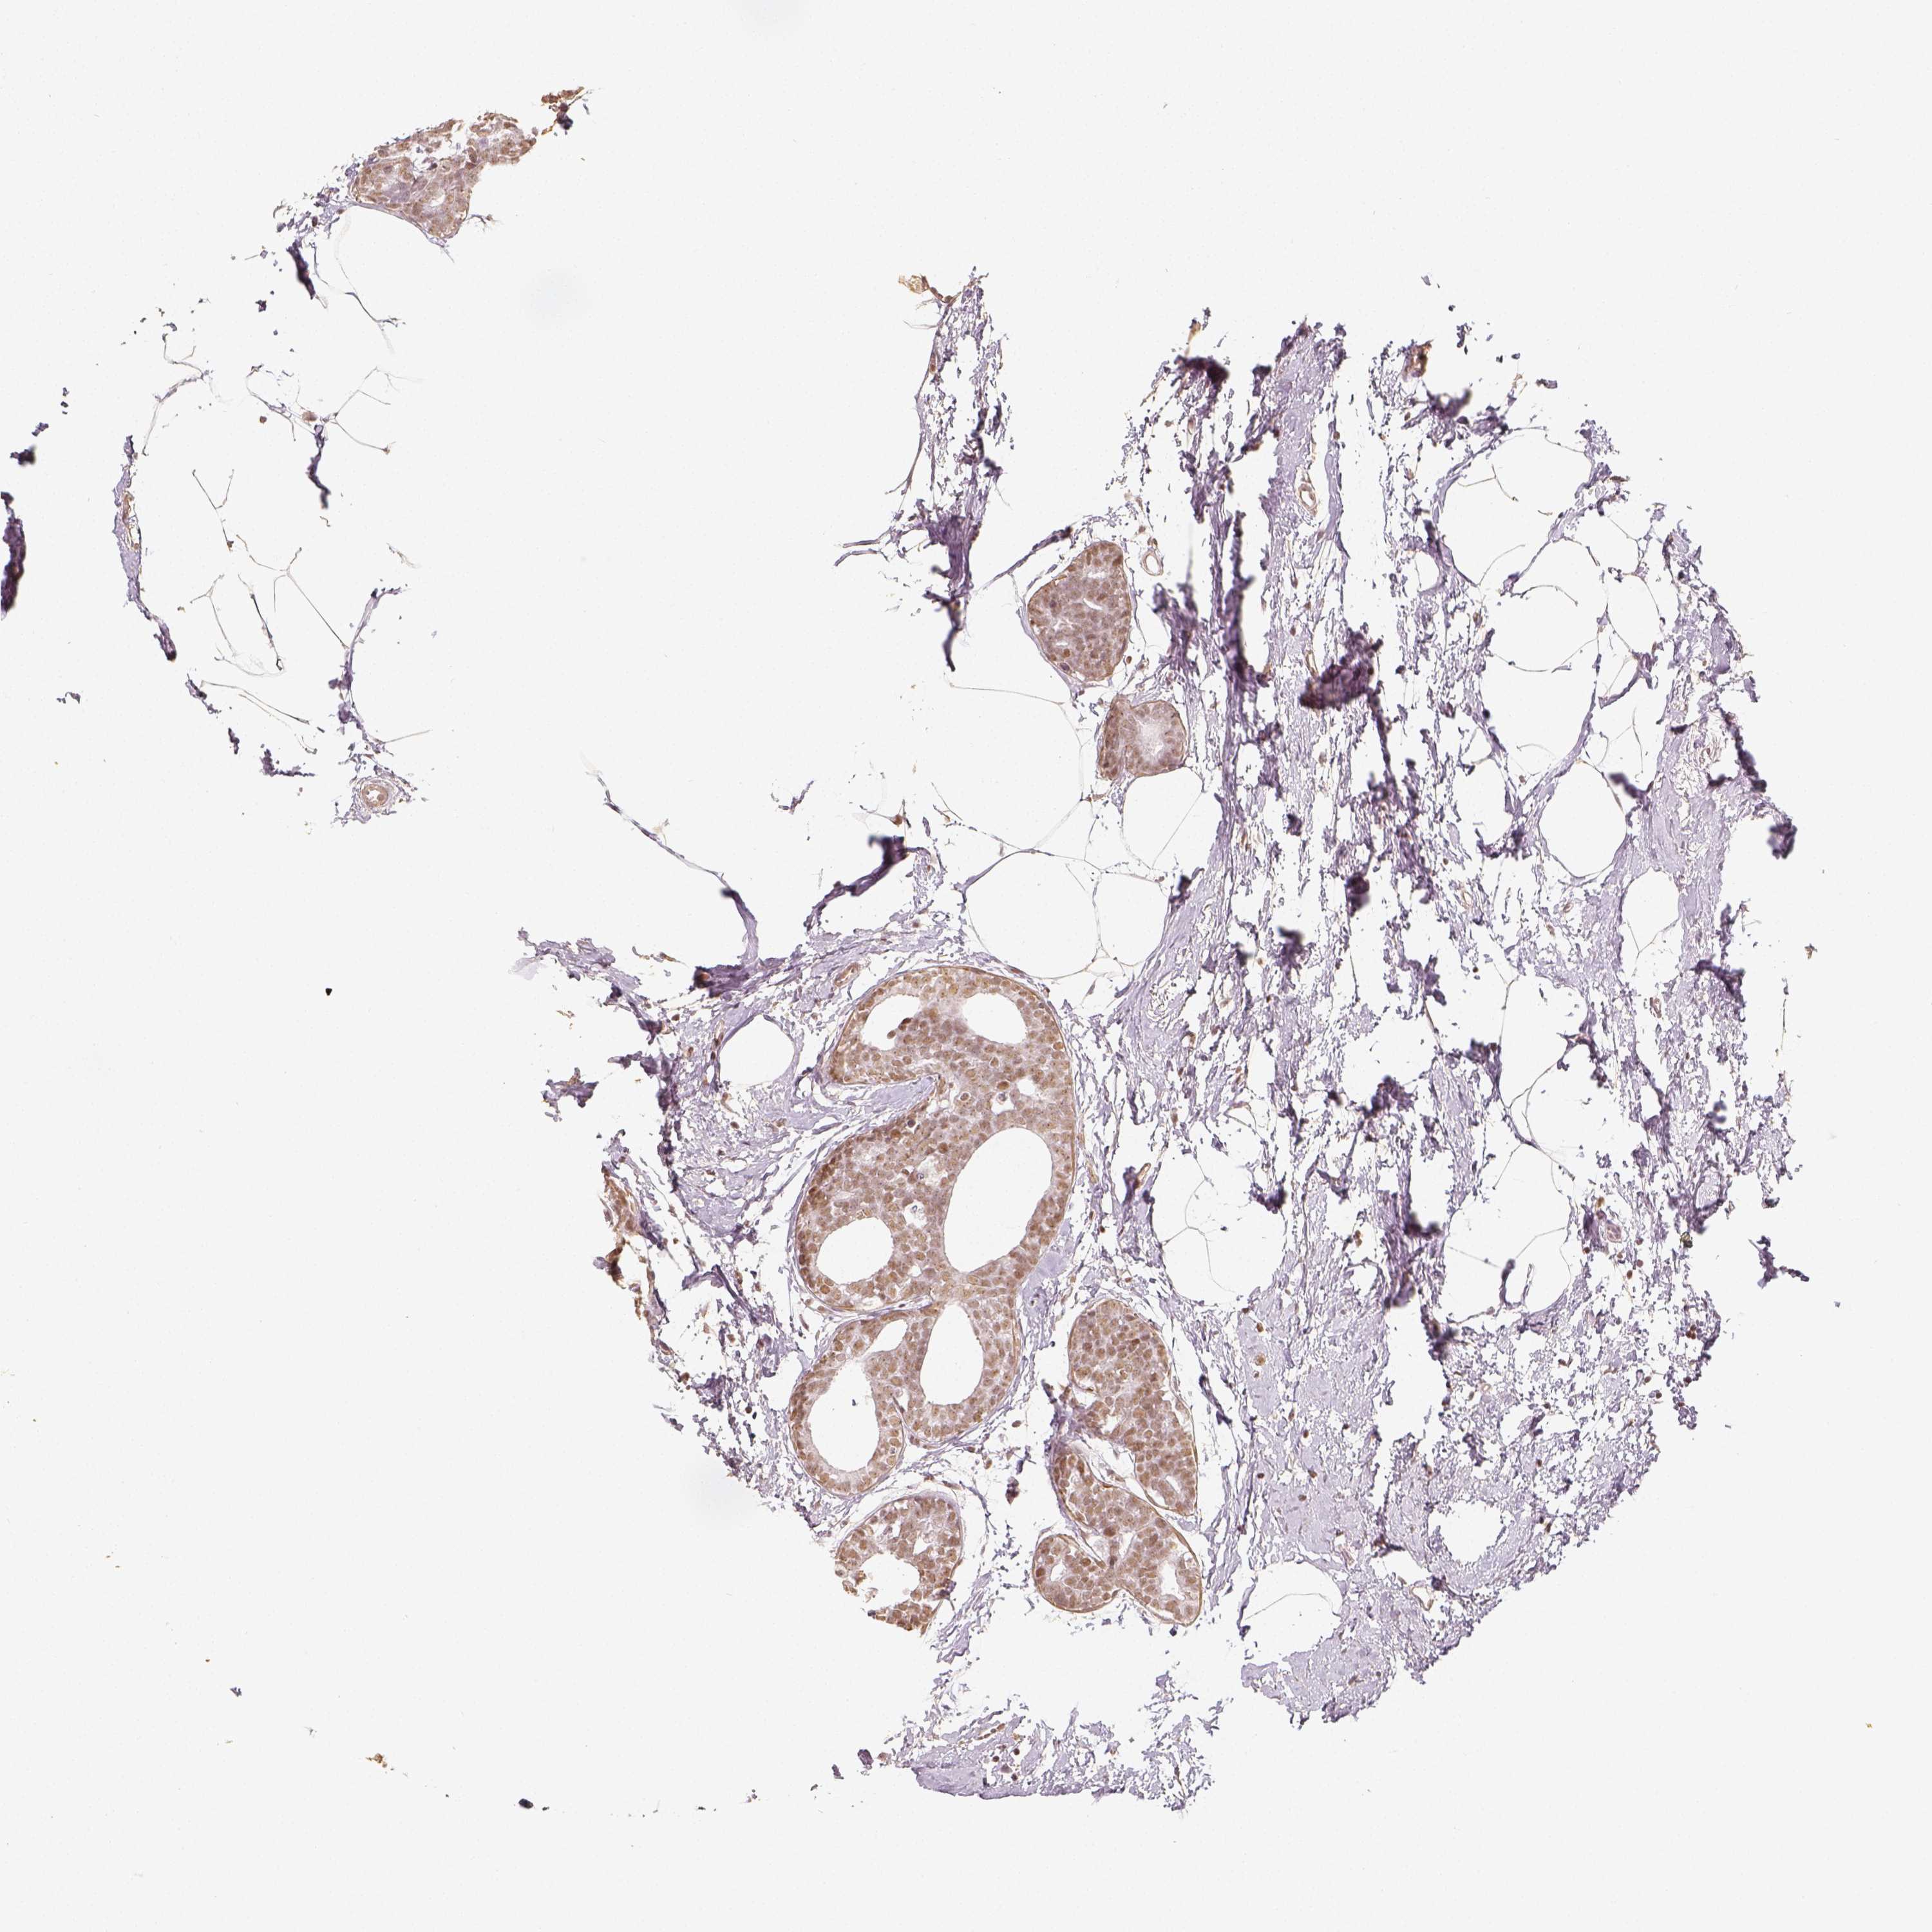

BRCA TCGA BRCA VALIDATION PROTEIN EXPRESSION

ANTIBODIES

AND

VALIDATION